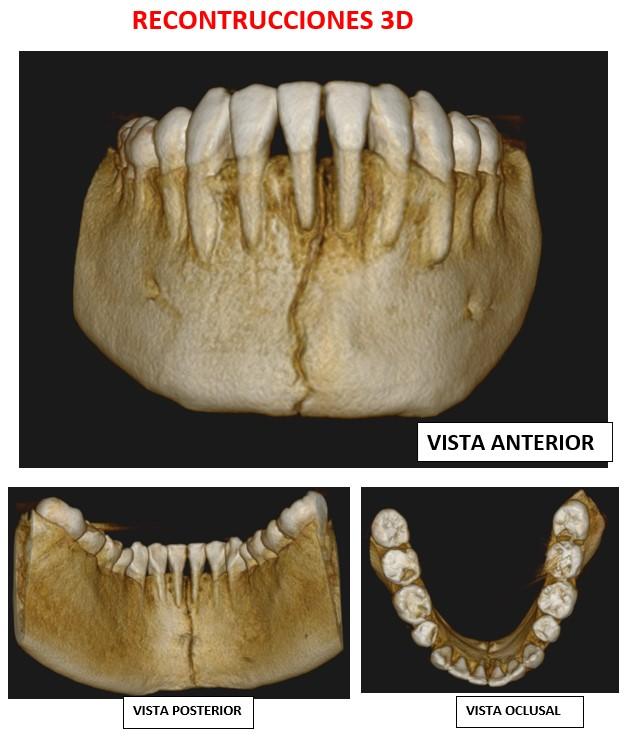

La presentación de casos radiográficos, permite la visualización de patologías que son muy difíciles de ver en la clínica, ya que muchos de ellos son hallazgos radiográficos. Además permite ver y refrescar clasificaciones y conceptos muchas veces estudiados. La presentación de los mismos no incluyen datos personales, mas que edad y sexo, que suelen ser importantes para ver la correlación entre la patología, su aparición o forma de presentación.

Esto también refleja las patologías que aquejan a los pacientes de nuestra región, y trata de ser un faro tanto para profesionales como alumnos que estudian dichas lesiones.